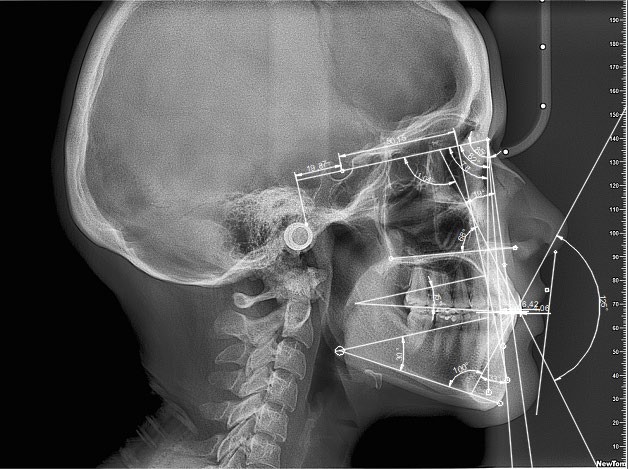

Las siluetas estéticamente aceptables fueron las que presentaron una puntuación mayor a 30, obteniendo un total de 23 perfiles considerados como agradables. Posteriormente se procedió a trazar el análisis cefalométrico de Steiner en el software AutoCAD 2023 (Figura 1).

Figura 1. Análisis de Steiner en el software AutoCAD 2023